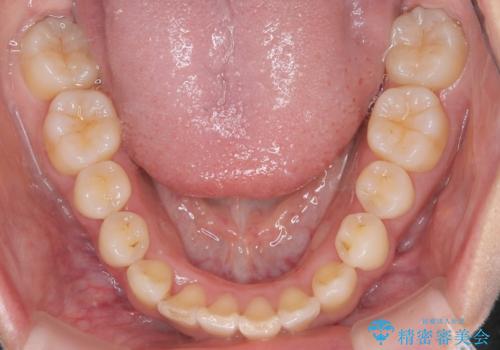

- 患者様は、全体的な歯列のガタガタとディープバイト(深い噛み合わせ)を主訴として来院されました。診断の結果、ディープバイトを改善するためには、歯列全体の拡大が必要であると判断しました。治療には、透明なマウスピース型矯正装置「インビザライン」を使用し、歯を適切に拡大しながら歯並びを整える計画を立てました。治療期間はおおよそ2年を見込んで進め、最終的に見た目にも大きく変化をもたらすことを目指しました。

ディープバイトの治療には、奥歯の高さや前歯の位置に対する繊細な調整が必要です。本症例では、インビザラインによる歯列拡大を行うことで、噛み合わせを改善し、歯並び全体を整えました。治療過程では、歯間のスペースを確保するため、IPR(インタープロキシマルリダクション)を適宜行い、無理なく歯列の調整を行いました。治療後は、歯並びが大きく改善され、患者様の見た目にも大きな変化が現れました。インビザラインは透明で目立たず、治療中の見た目を気にされる患者様にも配慮した治療法です。